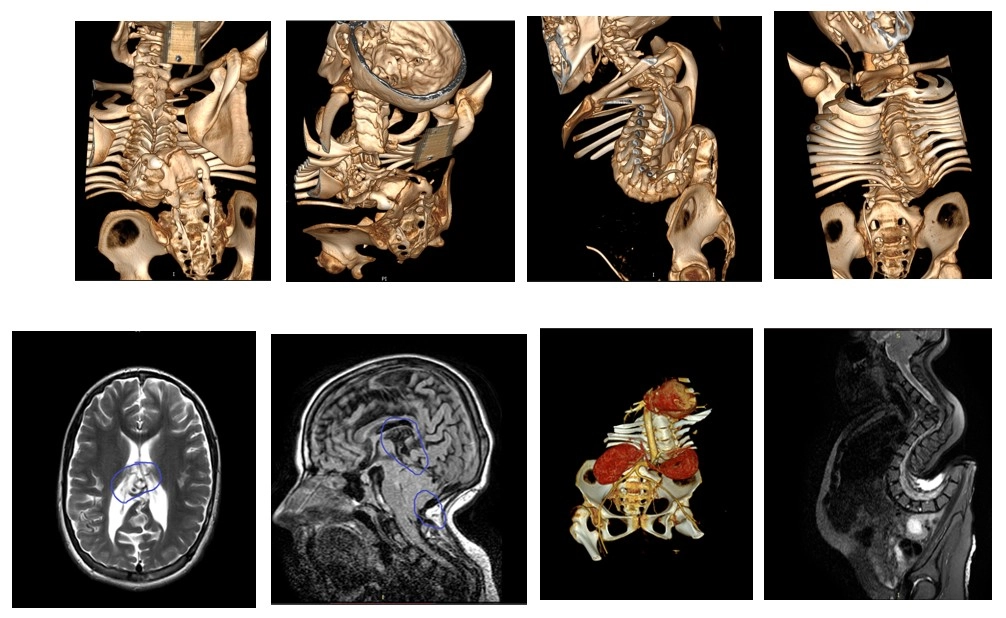

Диагноз:

Множественные врожденные аномалии головного, спинного мозга, позвоночника.

Тяжелый кифосколиоз грудопоясничного отдела позвоночника. Состояние после ВПШ. Артерио-венозная мальформация вены Галена. Аномалия Арнольда-Киари. Менингомиело-цистоцеле. Наружный ликворный свищ из зоны менингоцеле Th6-L1.

Нижняя параплегия. Верхний легкий парапарез.

Лечение:

Предварительно в течение 7 суток была проведена Halo – тракция.

Первым этапом была выполнена резекция L1, L2 и L3 позвонков. Установлена временная гибридная конструкция Th12-pelvic с редукцией таза.

Через 7 дней выполнен второй этап:

Иссечение ликворного свища. Пластика ТМО. Задняя вертебротомия. Окончательный спондилодез Th1-pelvic

До лечения и после:

• Задний спондилодез

Th1-таз.

• Резекция L1,2,3 позвонков.

• Пластика ТМО.

• Прямая коррекция таза на продольных коннекторах.